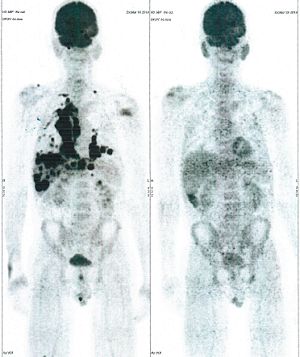

Below are some of the cases, from more than 80 cases we have treated so far with good results. When reading the PET/CT scans, the picture on the left is before treatment, and the picture on the right is after treatment. The intensity of black represents the activity of the cancer, but some black areas are not cancer: brain, heart, radioactive urine in bladder. For the heart, the intensity of black depends on the number of hours of fasting: if more than 10 hours, the heart is not even black, but if fasting is less than 6 hours, it is very black. The intensity of black in the brain can be variable in different scans depending on the brain activity at the time of the scan. The intensity of black in the radioactive urine can also be variable due to the hydration of patients and the time of injection of diuretic.

CASE NO: 9 (NHL + LUNG CANCER)

A middle-aged man successfully treated for non-Hodgkin’s lymphoma, came back with massive right lung and pleural cancer. After just 2 treatment, all the cancer went into remission. Treatment is continuing to prevent recurrence.

CASE NO: 10 (LUNG CANCER)

An old man with right lung cancer refused all cancer treatment, but was convinced to try our new cancer treatment because there is no severe side effect. After 3 treatment, the cancer shrunk to less than half the original size. He did not come back to continue the treatment.